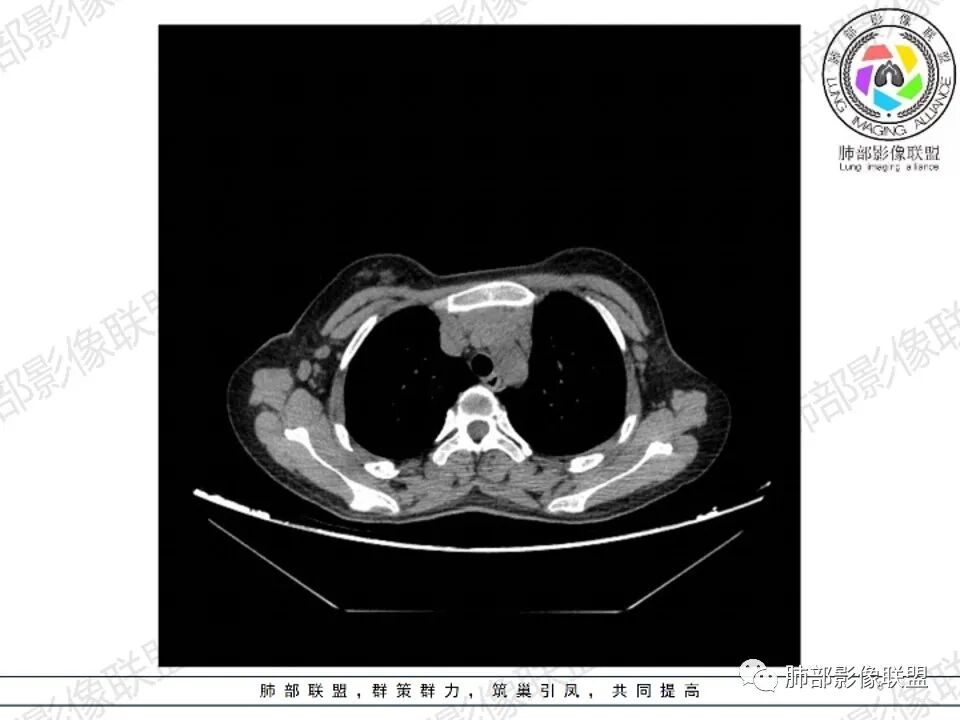

年轻女性,贫血,CT示前纵隔团片状软组织占位,多结节堆积感,塑形生长,边界欠清,包绕大血管及心包,增强明显不均匀强化,内见血管漂浮。纵隔4R,5,7区及双侧腋窝多发肿大淋巴结,综合考虑为淋巴瘤可能

前纵隔和双侧腋窝多发的淋巴结肿大,前纵隔为甚,融合呈中等强化,部分坏死呈低密度,包埋肺动脉主干和左心缘,融合斑块状,内见血管飘浮特点,前纵隔脂肪间隙混浊,首选淋巴瘤!

2.影像显示前纵隔不规则块状影,依势贴附心脏大血管旁,密度不均,边界不甚清楚,有结节融合感。

3.病灶轻度不均匀强化,可见血管穿行,散在液性低密度区。

4.双侧腋窝区见增大淋巴结,边界清楚。